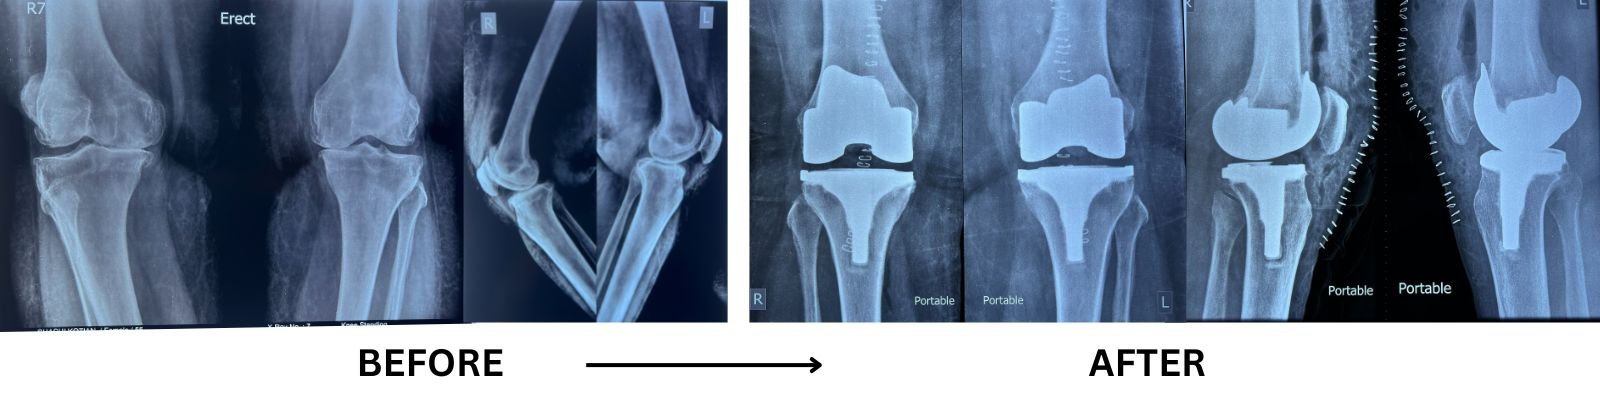

Total Knee Replacement

WHAT IS TOTAL KNEE REPLACEMENT

Knee replacement surgery (knee arthroplasty) is a procedure that involves removing diseased or damaged bone and cartilage of a knee joint and replacing them with artificial joint (prosthesis) made of metal, polymers or high-grade plastic parts.

TOTAL KNEE REPLACEMENT DIAGNOSIS